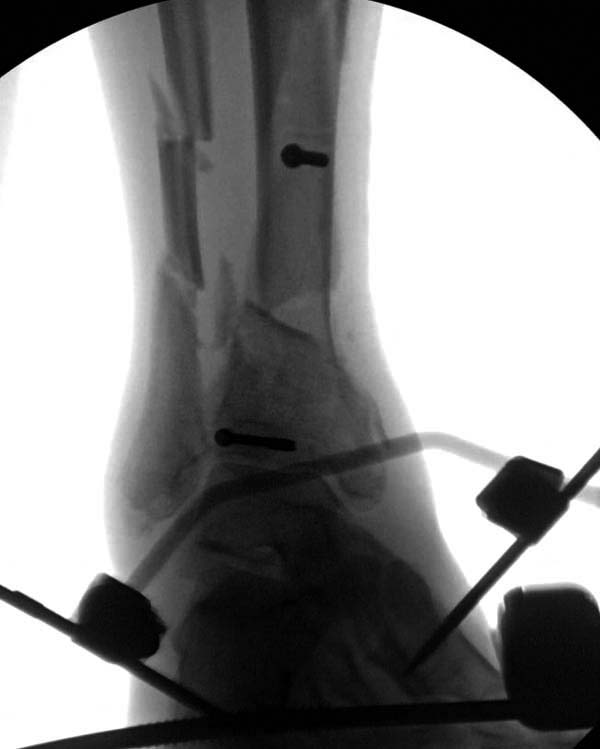

В нашем случае, травма в результате коллапса крыши. Открытый перелом. Ургентные Irrigation and Debridment, дистракция наружным фиксатором. В госпиталях первого уровня редко бывает изолированная травма, и на другой стороне повреждение стопы с переломом навикулярной кости. После обработки раны - вакуум и двухсторонние наружные фиксаторы.

Через три дня повторная I&D, где через рану манипулировали дистальным фрагментом с установкой пары межфрагментарных шурупов. На рану вакуум и следующая обработка закончилась закрытием раны. Отек держался немного дольше, чем обычно.

После спадения отека вариантов фиксации много, включая мининвазивную технику, но данный случай закончили установкой простого аппарата Илизарова.